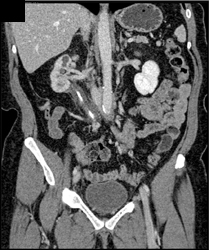

Retroperitoneal Fibrosis